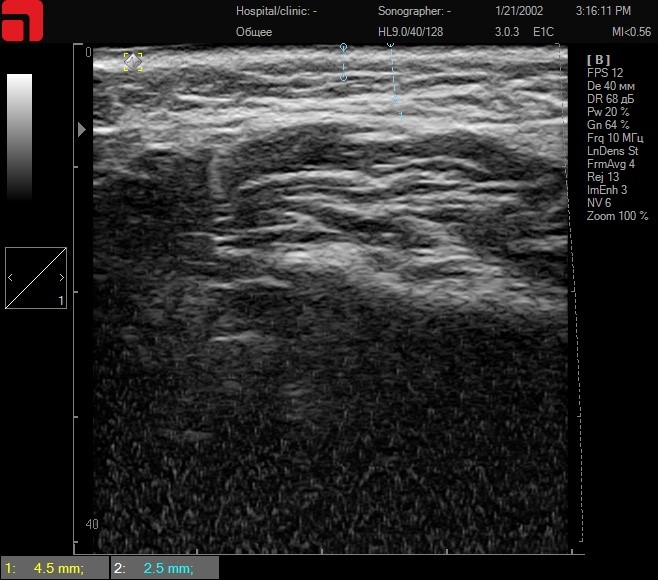

Далее проводится сканирование с определением глубины залегания СМАС-слоя, общее содержание соединительной ткани в подкожно-жировой клетчатке в щечной и околоушно-жевательной области (Рис.3.). Именно на этом этапе определяется, какие насадки будут использоваться для лифтинга щечной области, уменьшения выраженности «брылей», морщин «марионеток», носогубных складок. У данной пациентки отмечается большое количество соединительной ткани в подкожно-жировой клетчатке и выраженный SMAS – хорошие прогностические признаки. В протоколе процедуры важно использовать и манипулу M7 3 мм – для уплотнения и сокращения коллагена в ПЖК, и манипулу 4,5 мм D4 – для укрепления соединительной ткани SMAS.

Сканирование щечной области

Рис. 3. Сканирование щечной области.